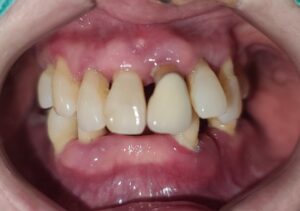

위 환자분은 상, 하악 다수의 치아가

상실된 상태로 내원해 주셨습니다.

잇몸이 좋지 않아 하나씩 발치를 하다 보니

남은 치아가 몇 개 없어 식사하시는데

큰 불편함을 호소하셨는데요.

전체적으로 어금니 부위 예후가 좋지 않았고

남아 있는 치아들도 오래 사용하기엔

무리가 있을 것이라고 판단하여